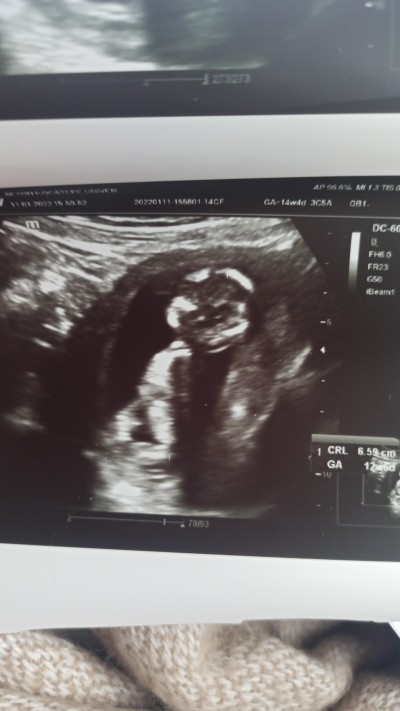

image

Burda 12 haftalık

kız :) tabi rabbim bilir yinede. Allahım kucağına almak nasip eylesin inşallah ♡♡

Bildiniz vallahi kızım olacakmış :)